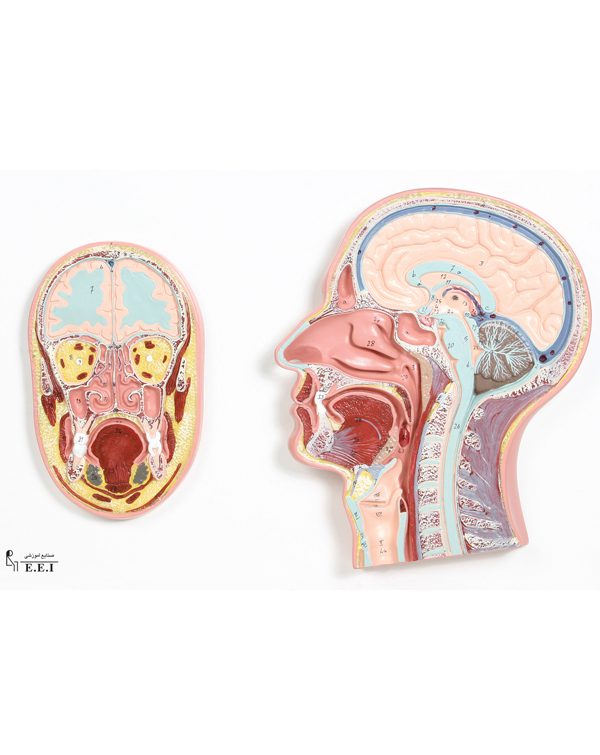

مولاژ کلمه ای فرانسوی به معنای قالب است. آناتومی بدن انسان با تجهیزاتی مانند مولاژهای پزشکی یا کالبدشناسی که نمونه هایی تخصصی و شبیه به اندام های بدن انسان هستند، به دانش آموزان و دانشجویان آموزش داده می شود. استفاده از مولاژ در روند یادگیری و آموزش تاثیر به سزایی داشته و تمامی اندام ها را با تمامی جزئیات و با کیفیت بالا می توان مشاهده و بررسی کرد. مولاژها عموما از جنس PVC نشکن، لاستیک یا فوم ساخته شده و دارای رنگ طبیعی و قابل شست و شو هستند. برخی از انواع مولاژها مناسب برای آموزش مراقبت های پزشکی و پرستاری است و امکان تمرین بانداژ، تزریق، CPR، جراحی و... وجود دارد. مولاژها معمولا هر کدام عضوی از بدن را نمایش می دهند و قابلیت تفکیک و مشاهده همه بخش های آن وجود دارد.

مولاژها معمولا با توجه به نوع اعضا و یا دستگاه های بدن در اندازه طبیعی، کوچکتر و یا چندین برابر بزرگتر ساخته می شوند تا امکان مشاهده دقیق اجزای آن ها فراهم شود. برخی مولاژها از چندین قطعه ساخته شده اند که قابلیت تفکیک دارند. علاوه بر نمایش ساختار و نحوه عملکرد اعضای بدن، ماهیچه ها و عضلات بدن را نیز می توان به کمک مولاژها مشاهده کرد.

مولاژها ابزاری تخصصی برای آموزش دانشجویان پزشکی، دندان پزشکی، پرستاری و مامایی است. همچنین در مدارس و سایر مراکز آموزشی میتوان از انواع مولاژها برای بهبود یادگیری و آموزش بهره برد. در کلینیک های زنان و زایمان، دندان پزشکی، سالن های تشریح، بیمارستان ها و آزمایشگاه ها نیز مولاژهای مراحل حاملگی، انواع دندان و بیماری های آن کاربرد دارند.